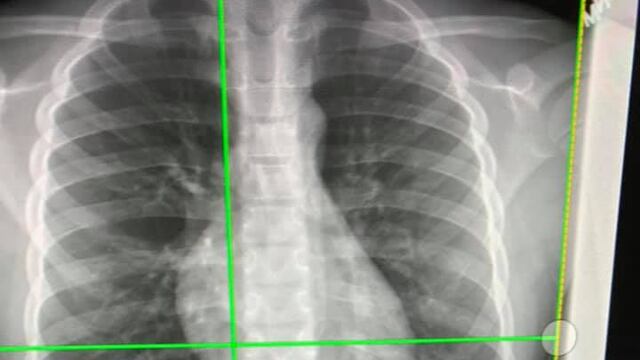

Por fortuna, en el hospital le dieron buenas noticias: Una radiografía mostró que el AirPod viajó por toda la garganta de QJ sin afectar ninguno de sus órganos, hasta llegar a los intestinos, por lo que debían esperar a que continuara su tránsito hasta ser expulsado, como cualquier otro desecho. Después de ello, el niño fue dado de alta.